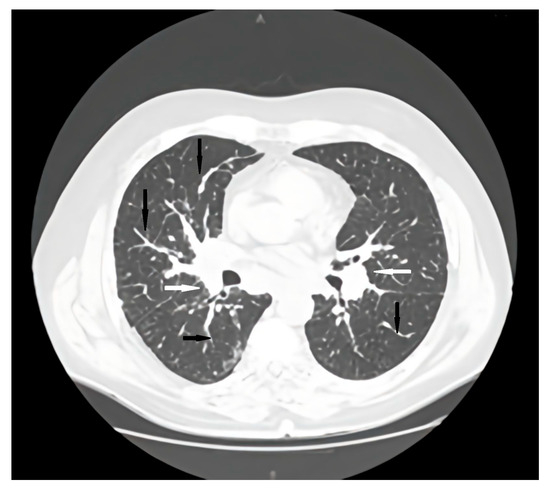

Association Between Common Variable Immunodeficiency and Pulmonary Amyloidosis: Review

by Cristina Maria Radu, Irena Nedelea, Vlad Andrei Ardelean, Adriana Parau and Milena Adina Man

J. Clin. Med. 2026, 15(4), 1446; https://doi.org/10.3390/jcm15041446 - 12 Feb 2026

Background: Common variable immunodeficiency (CVID) is the most frequent symptomatic primary antibody deficiency, associated with recurrent infections, immune dysregulation, and non-infectious complications. Amyloidosis is a rare but severe complication with pulmonary involvement being exceptional. Objective: The aim of this study was to review [...] Read more.

Background: Common variable immunodeficiency (CVID) is the most frequent symptomatic primary antibody deficiency, associated with recurrent infections, immune dysregulation, and non-infectious complications. Amyloidosis is a rare but severe complication with pulmonary involvement being exceptional. Objective: The aim of this study was to review reported cases of amyloidosis complicating CVID and present a unique case of pulmonary involvement. Methods: A literature research identified observational studies and case reports linking amyloidosis with CVID. Additionally, we describe a patient with CVID complicated by pulmonary and gastrointestinal amyloidosis. Results: Fifteen cases were identified, mostly amyloid A (AA) with multiple organ involvement. Only one case of pulmonary amyloidosis was reported. To date, no cases of pulmonary light-chain amyloidosis (AL) have been described in CVID patients without an underlying plasma cell dyscrasia. Our patient initially presented with AA amyloidosis but evolved to systemic AL type with rapid progression and fatal outcome despite therapy. Conclusions: Amyloidosis should be considered in CVID patients with atypical symptoms. Accurate amyloid typing is essential as treatment differs between AA and AL types. Early recognition may improve outcomes. Full article

Show Figures

Figure 1